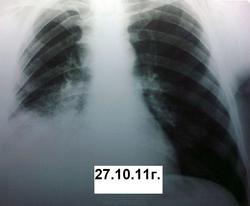

Вот такая динамика. Первый снимок я добыл позже. Между первым и вторым пациент лечил пневмонию в домашних условиях. В дальнейшем ее же в условиях стационара без финансовых и лекарственных ограничений.

Оказываетя, что за год до этого пациенту была удалена опухоль на бедре, гистологически синовиальная саркома. Было произведено КТ ОГК. Подтвердили пневмонию, мета в позвоночник.

Не зная, что была такая операция (больной вначале это притаил, видимо не хотел к этому возвращаться) я предположил БАР, но компъютерщики развеяли мои подозрения. Поэтому я бы хотел знатоков КТ-дела проанализировать сканы, все ли там в порядке с корнем и т.д.

Пневмонии тут нет никаким боком. Не было КТ - высказался бы за БАР. На КТ, в легких -типичный раковый лимфангаит (кстати, слева тоже, еще чуть-чуть и полыхнет). Так что, 100% метастазирование. И это кроме очевидного метастаза в позвонок. А корень надо оценивать в "медиастинальном" окне.